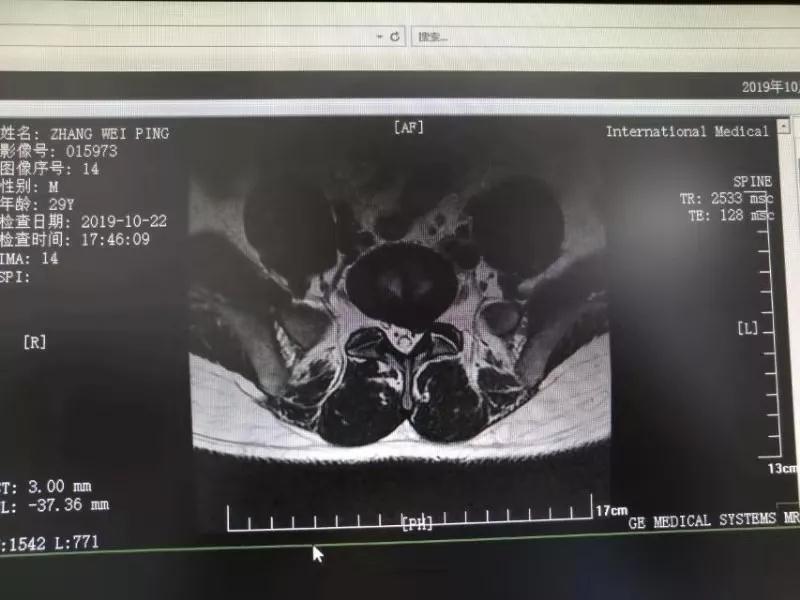

10月25日,29歲的患者小張了解到西安國際醫(yī)學(xué)中心骨科醫(yī)院專家云集,一大早便在家人的陪同下,來到西安國際醫(yī)學(xué)中心骨科醫(yī)院就診?!拔已闯掷m(xù)2年多,最近感冒后腰痛癥狀明顯加重了?!毙埫媛犊喑?,因為長期腰痛、左下肢放射性疼痛,她晚上睡覺不能平躺,經(jīng)常疼得睡不著,需要口服止痛藥物才能有所緩解。走路走不了多遠(yuǎn)就開始腿抽的疼,嚴(yán)重影響到工作和生活。

結(jié)合患者的檢查以及年齡情況,王自立副院長推薦讓專門研究椎間孔鏡技術(shù)王雄勛主任給小張做微創(chuàng)的椎間孔鏡手術(shù)。該手術(shù)創(chuàng)傷很小,不影響脊柱的穩(wěn)定性,尤其適合于椎間盤突出的年輕患者,懷著對骨科醫(yī)院專家的信任,小張與家人商議后,接受手術(shù)治療。